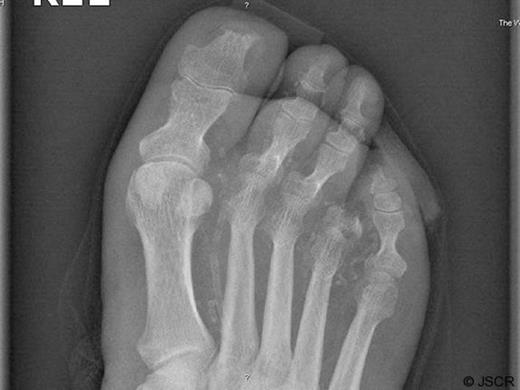

The procedure was performed under regional anaesthesia, with a racket incision centred over the fourth metatarsophalangeal joint necessary to excise the fourth digit. The incision began 1 cm proximal to the metatarsophalangeal joint and passed distally to the base of the proximal phalanx which was divided to pass around the toe and across the plantar surface at the level of the flexor crease. The amputated segment was removed and sent to the laboratory for microbiological microscopy, culture and sensitivity analyses. The skin of the third and fifth toes adjacent to the fourth toe was debrided as necessary, although no further amputation was required. We opted to close this wound by constructing a tissue flap rather than leaving the wound to granulate by secondary intention. In this instance we utilised the fifth digit as a novel osteo-myocuteanous flap, rather than using conventional techniques. As can be seen from the x-ray studies performed postoperatively, we modified standard myocutaneous flap construction techniques by incising the medial border of the fifth digit to the periosteum, which was then mobilised to the superior / inferior surface of the fifth phalanxes, with the bone remaining in-situ (Figure 1).

Postoperative x-ray of the right foot demonstrating the amputated fourth toe. The Xray also demonstrates the phalanxes of the fifth toe being used to construct the flap used to close the defect.